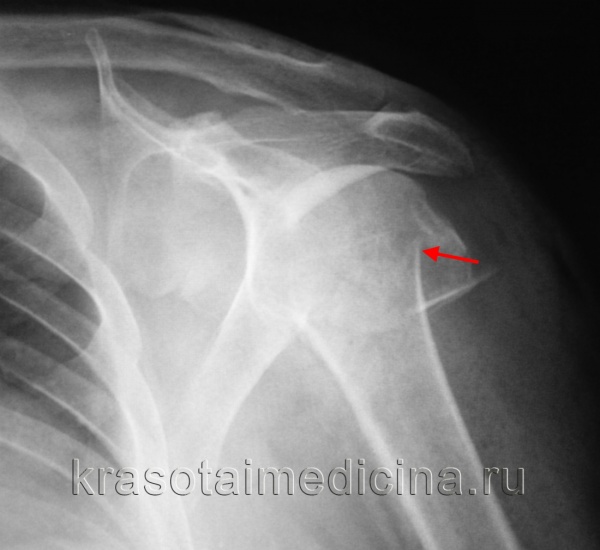

Рентгенограмма: перелом шейки лопатки (красная линия) и основания акромиального отростка (зеленая линия).